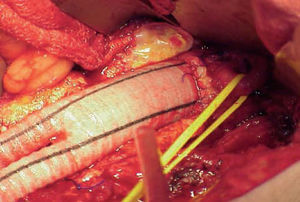

Revascularization surgery. Diffuse, extensive involvement is usually best treated by placement of an aortic-unifemoral or -bifemoral prosthesis (Figures 5 and 6). The effects of this well-systematized technique are known. The results in terms of permeability are above 85% and 80% at 5 and 10 years, with operative mortality below 5%.4 However, the technique involves major arterial surgery and requires quantifying the surgical risk to select the most suitable candidates. The operation in patients at high risk or who have a hostile abdomen (multiple reoperations, prior radiotherapy, active infection, etc) is carried out by means of what is referred to as "extraanatomic techniques," which enable revascularization of the limbs via non-anatomic pathways, and with less aggression. The most commonly used are axilo-unifemoral or -bifemoral, and femorofemoral bypass surgery. Both types of bypass surgery are performed via a subcutaneous tunnel, the former via the lateral region of the thorax and the abdomen, and the latter via the suprapubic region. They can be done with locoregional anesthesia. The figures for permeability with extraanatomic bypass surgery are lower, ranging between 40% and 70% at 5 years, depending on the clinical indication.4 They are, therefore, rarely indicated in the absence of critical ischemia.

Figure 5. Arteriography showing extensive aortoiliac occlusion and the result after aortobifemoral bypass surgery.

Figure 6. Image of a Dacron prosthesis with infrarenal anastomosis. Control of left renal artery with elastic tape.